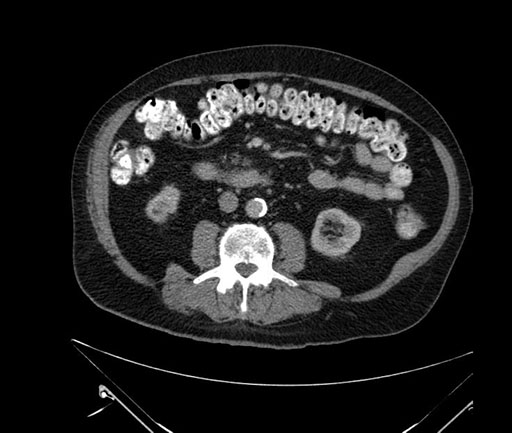

Whipple (pancreaticoduodenectomy) [case 7]

Imaging Analysis

Look through the patient's CT scan to identify any areas of concern for the necessary procedure.

Based on your CT findings, which issue(s) would give reason for "planned slowing down moment(s)" in this case?

Considering a standard Whipple procedure, what step(s) of the operation would you do differently in this case?